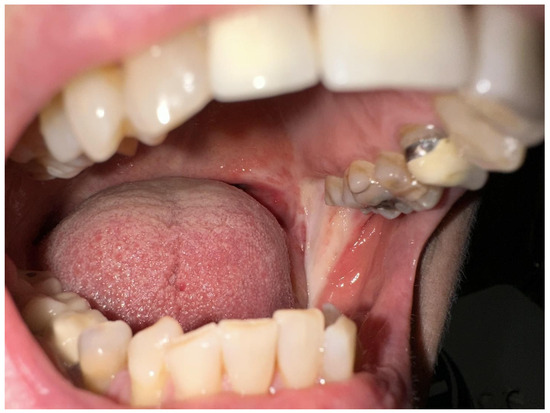

2. Detailed Case Description